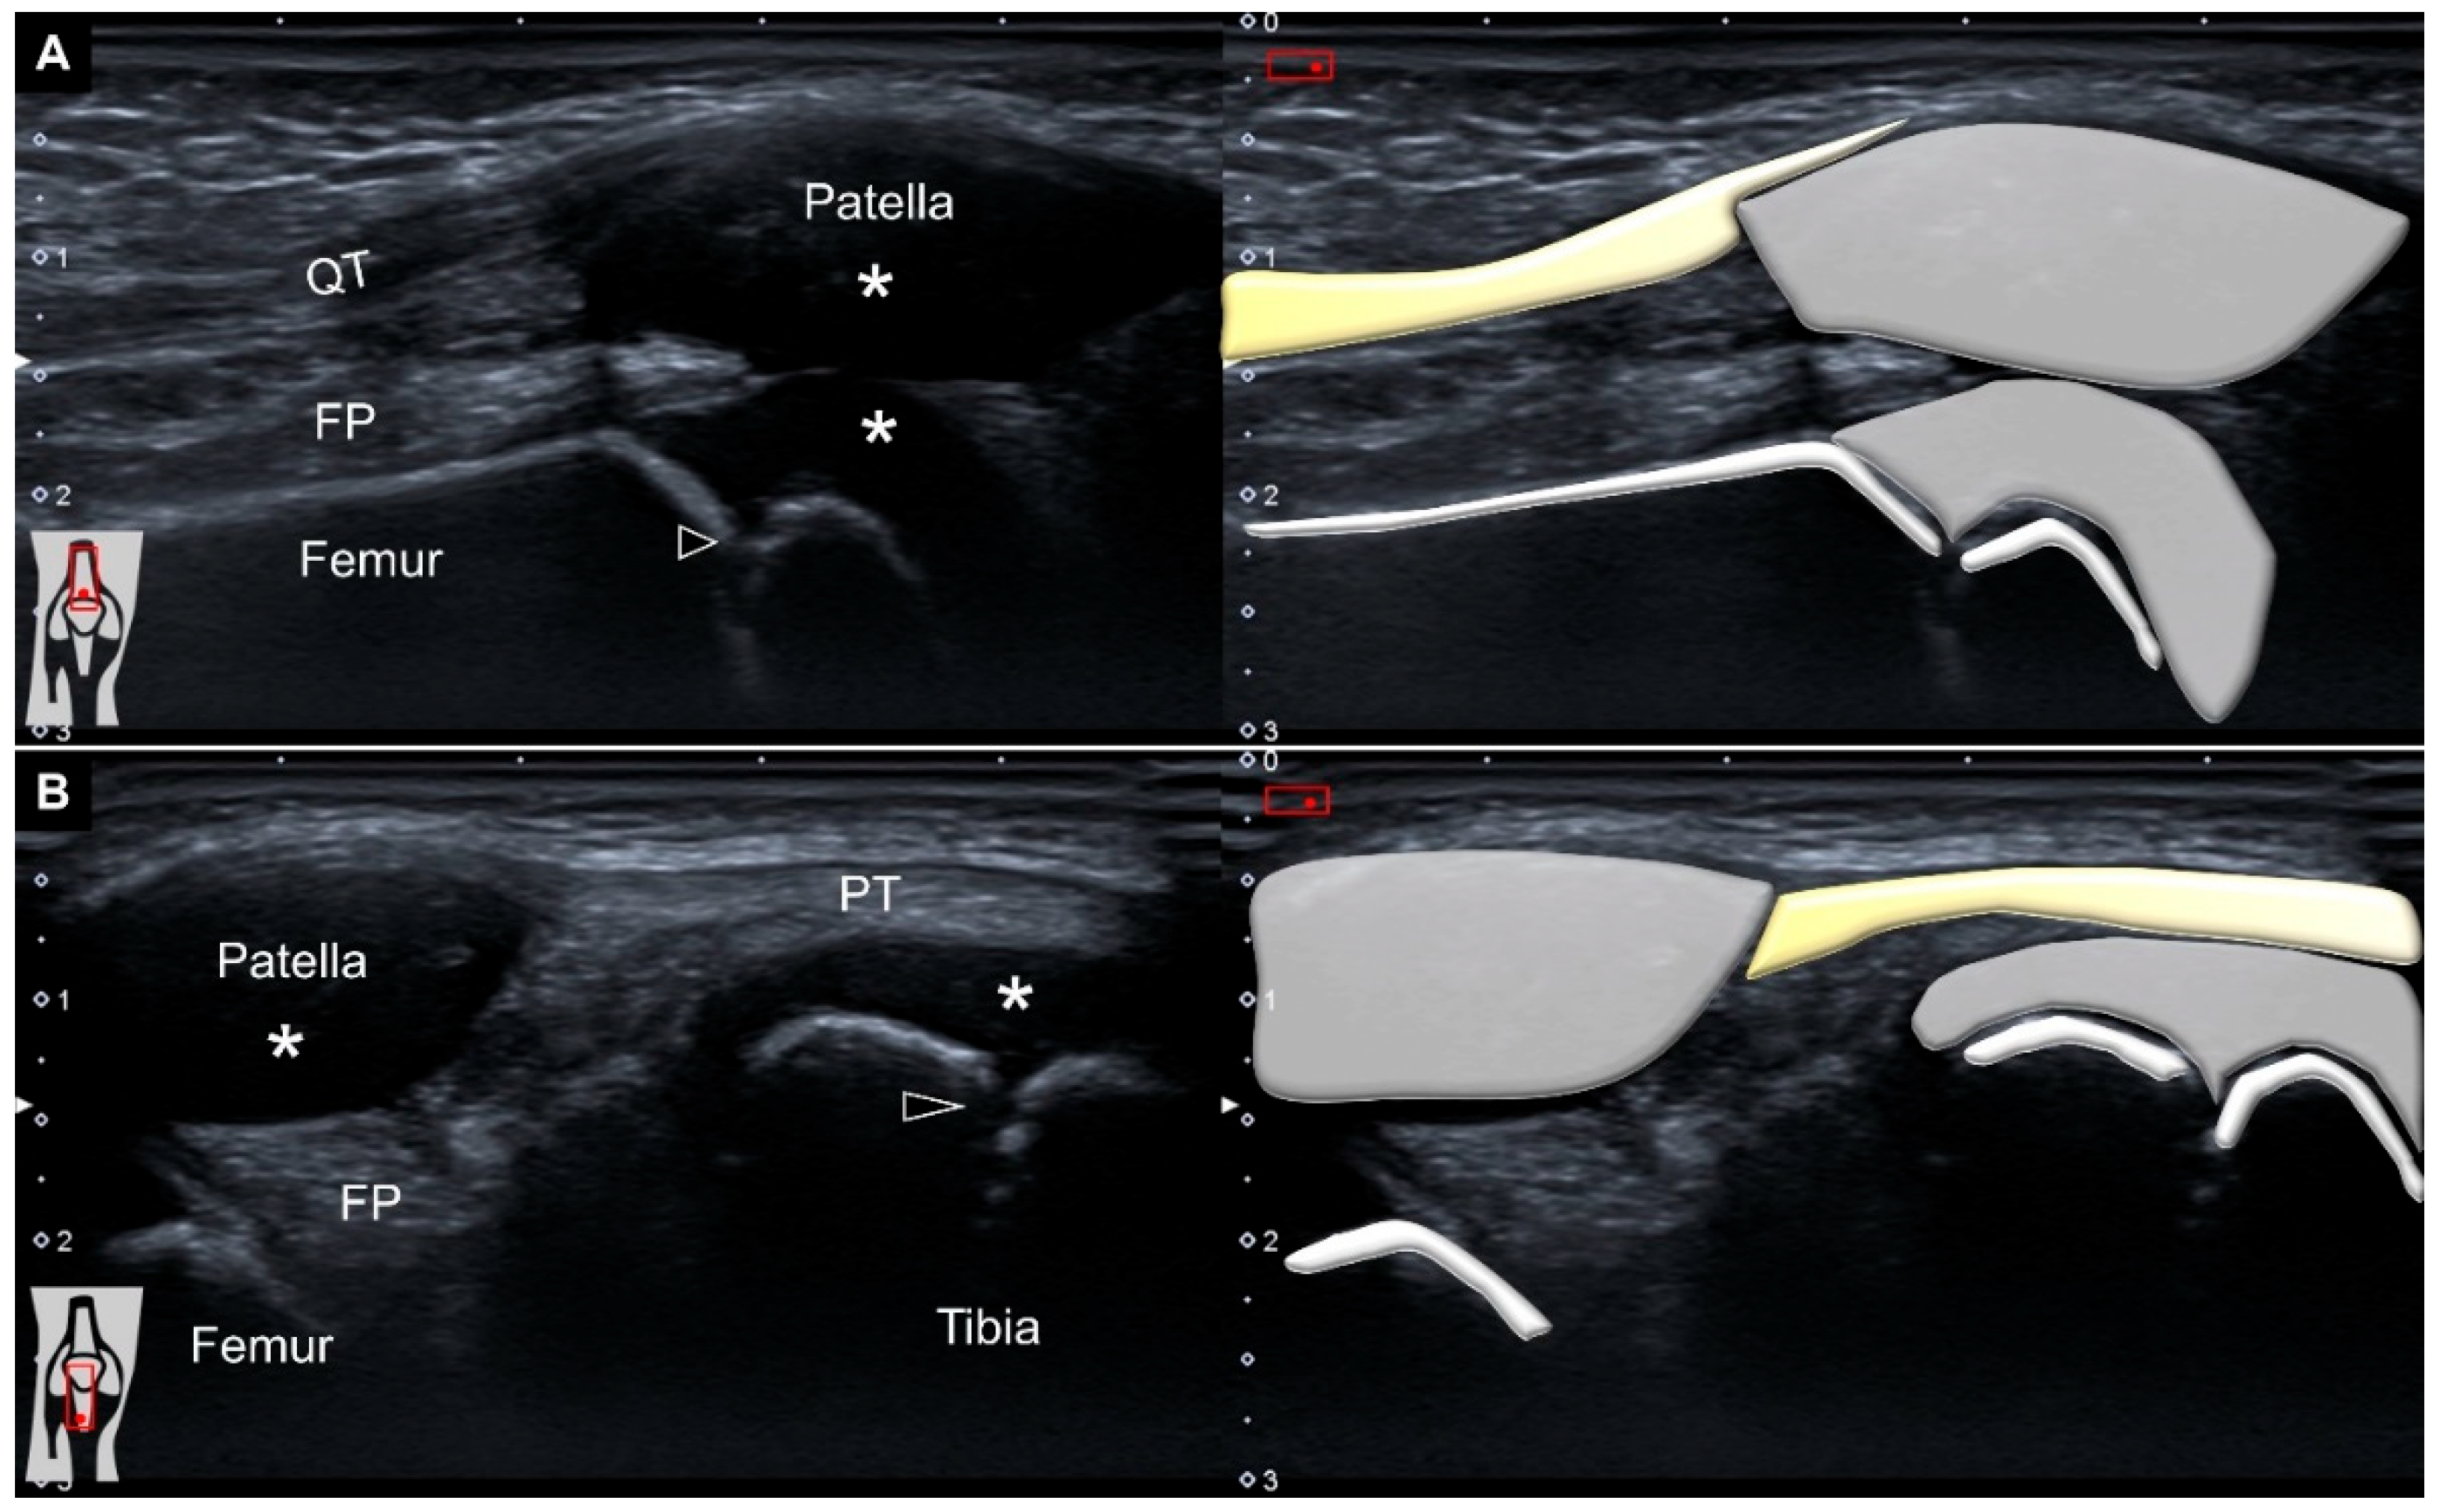

Ultrasound imaging showed an ill-demarcated hyperechoic mass protruding next to the cartilage overlying the distal femur towards the subcutaneous layer through a slit over the lateral patellar retinaculum (Figure 3A and Video S1). No increased vascularity was visualized inside or surrounding the lesion (Figure 3B). Repositioning the knee back to extension while lying supine, the mass was seen sinking to the space underneath the lateral patellar retinaculum (Figure 3C). Accordingly, herniation of the fat pad through a defect in the lateral patellar retinaculum was diagnosed.

Figure 3. Hyperechoic fat pad (white arrowheads) was seen protruding through a defect in the lateral patellar retinaculum (black arrows) (A). There was no vascularity surrounding or inside the protruded fat pad during squatting (B). The fat pad was visualized sinking underneath the lateral retinaculum upon knee extension (C). *: hyaline cartilage.